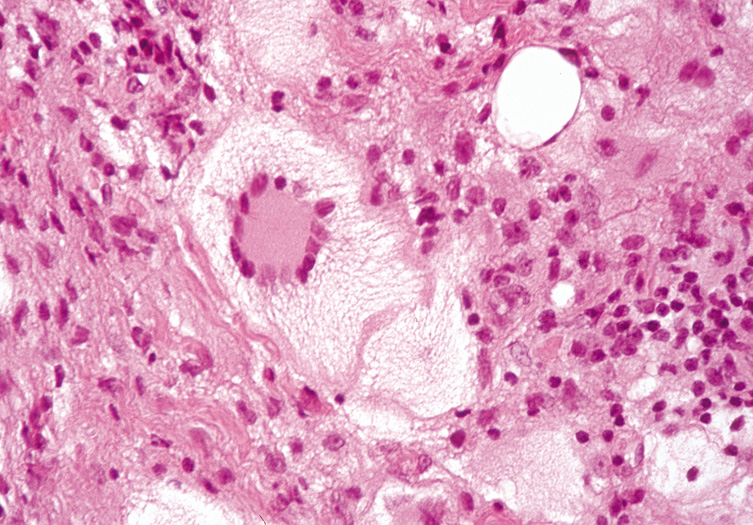

Xanthogranulomas are often a manifestation of an underlying systemic condition. Erdheim-Chester disease presents with xanthelasma, and xanthogranulomas (Fig. 13). Juvenile xanthogranuloma may be single or multiple, orange-hued, firm papulonodules on the face. They may be present at birth, but most often arise in infancy. There is a dense diffuse dermal inflammatory infiltrate characterized by large Touton multinucleated giant cells with an amphophilic center surrounded by a ring of nuclei surrounded by an external ring of foamy cytoplasm. Most lesions involute spontaneously. Xanthogranulomas may appear on the iris and produce hemorrhage and glaucoma.

Fig. 13. Erdheim–Chester Disease—This xanthogranulomatous disease is characterized by dermal infiltrate of fibrohistiocytes and Touton giant cells. The histiocytic cells are S-100 negative. (Photos courtesy of William Morris, M.D.)

Histologically, early lesions show a dense collection of histiocytes, some of which have pale, vacuolated cytoplasm. There also is an inflammatory infiltrate of lymphocytes and eosinophils. Mature lesions show the characteristic foam cells and Touton giant cells. Touton giant cells have a central wreath of nuclei surrounded by foamy cytoplasm (Fig. 14). In late lesions, the infiltrate is replaced by fibrosis.

Fig. 14. Xanthogranuloma—This Touton giant cell is characterized by a homogeneous eosinophilic center surrounded by a circle of multiple nuclei that is, in turn, surrounded by a large foamy ring (hematoxylin and eosin stain). (Photos courtesy of William Morris, M.D.)